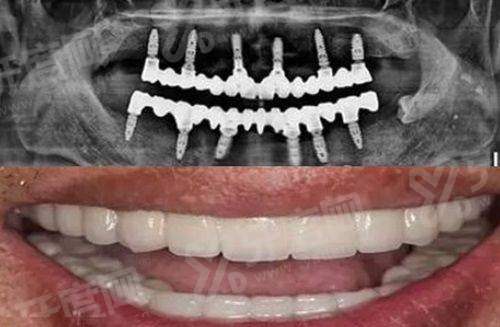

1、邵阳雅贝康口腔医院医院引进了数字化口腔CBCT设备,能够清晰地显示牙齿、牙槽骨等口腔内部结构,为种植牙、牙齿矫正等治疗提供精细的影像支持,提高治疗的正确性和成功几率。

2、邵阳雅贝康口腔医院采用数字化种植技术,通过3D导板导航进行种植手术,手术创伤小、修复快,大大减轻了患者的痛苦,让种植牙过程更加舒适。